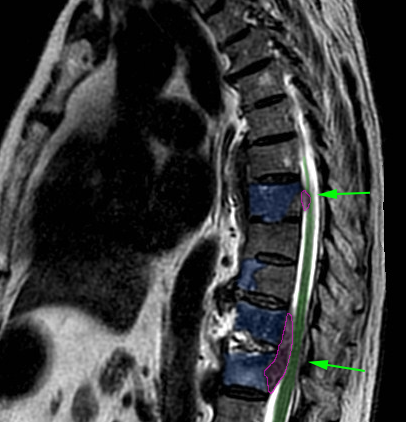

Πολλαπλές μεταστάσεις σπονδυλικής στήλης τόσο στα σώματα των σπονδύλων όσο και εντός του σπονδυλικού σωλήνα (φούξια) με πίεση στο νωτιαίο μυελό (πράσινα βέλη). |